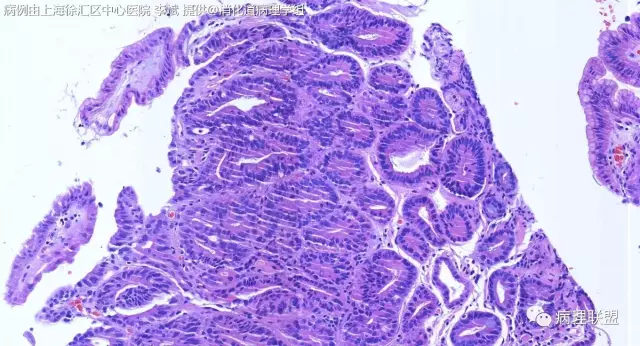

@李斌,高级别,腺体结构乱复杂,核异型性大,极向乱

北医三院 石雪迎

@左淑英 子宫内膜受激素周期影响,腺体结构和上皮变化比较大,消化道受损伤、炎症等影响比较大,同样要看结构、看细胞,但标准确实不大一样。虽然具体病例需要具体分析,但我感觉在胃肠道,对于判断时感觉模棱两可的病例,表面成熟现象是区分反应性增生和低级别异型时可重复性相对比较好的指标;核极向是区分高低级别异型增生时可重复性相对比较好的指标。供参考